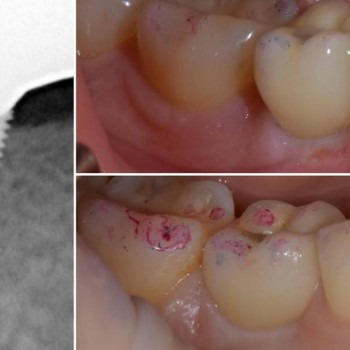

Стоматолог

Основная специальность: Стоматолог

Дополнительные специализации: Стоматолог, стоматолог-имплантолог

Ключевые направления: стоматология

Лечение кариеса от 1100 грн.

Установка фотополимерной пломбы от 1150 грн.

Глушко Назар Романович. Напрямки роботи: відбудова кісткової тканини щелеп, пластика ясен довкола зубів та імплантатів, імплантація зубів, протезування на зубах та імплантах. Учасник численних конгресів, конференцій, навчальних курсів в Україні та за кордоном. Член міжнародної організації ITI. Консультант компанії Megagen. Опініон лідер компанії Geistlich (Швейцарія). Автор навчальних курсів для стоматологів по дентальній імплантації та пластиці.